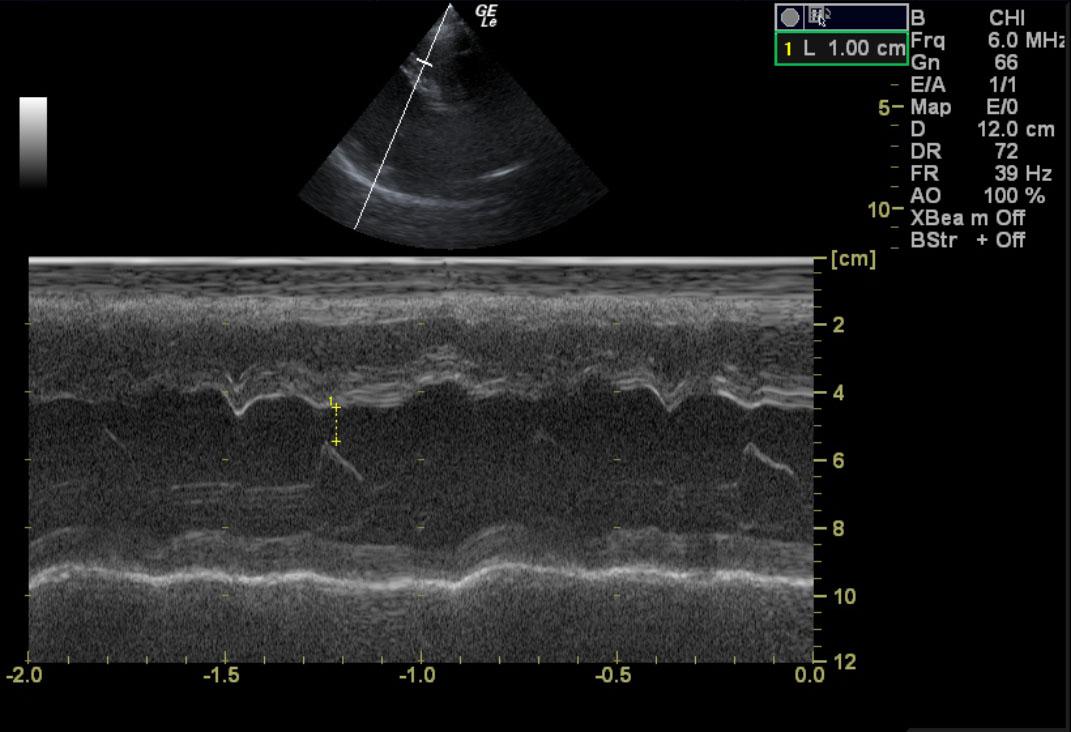

A 6-year-old NM Boxer dog was presented for lethargy, cough, tachypnea, exercise intollerance. Physical exam revelaed a 2/6 left sided heart murmur and mild tachypnea and arrhythmia. The only abnormality on laboratory work was elevated amylase and creatinine.